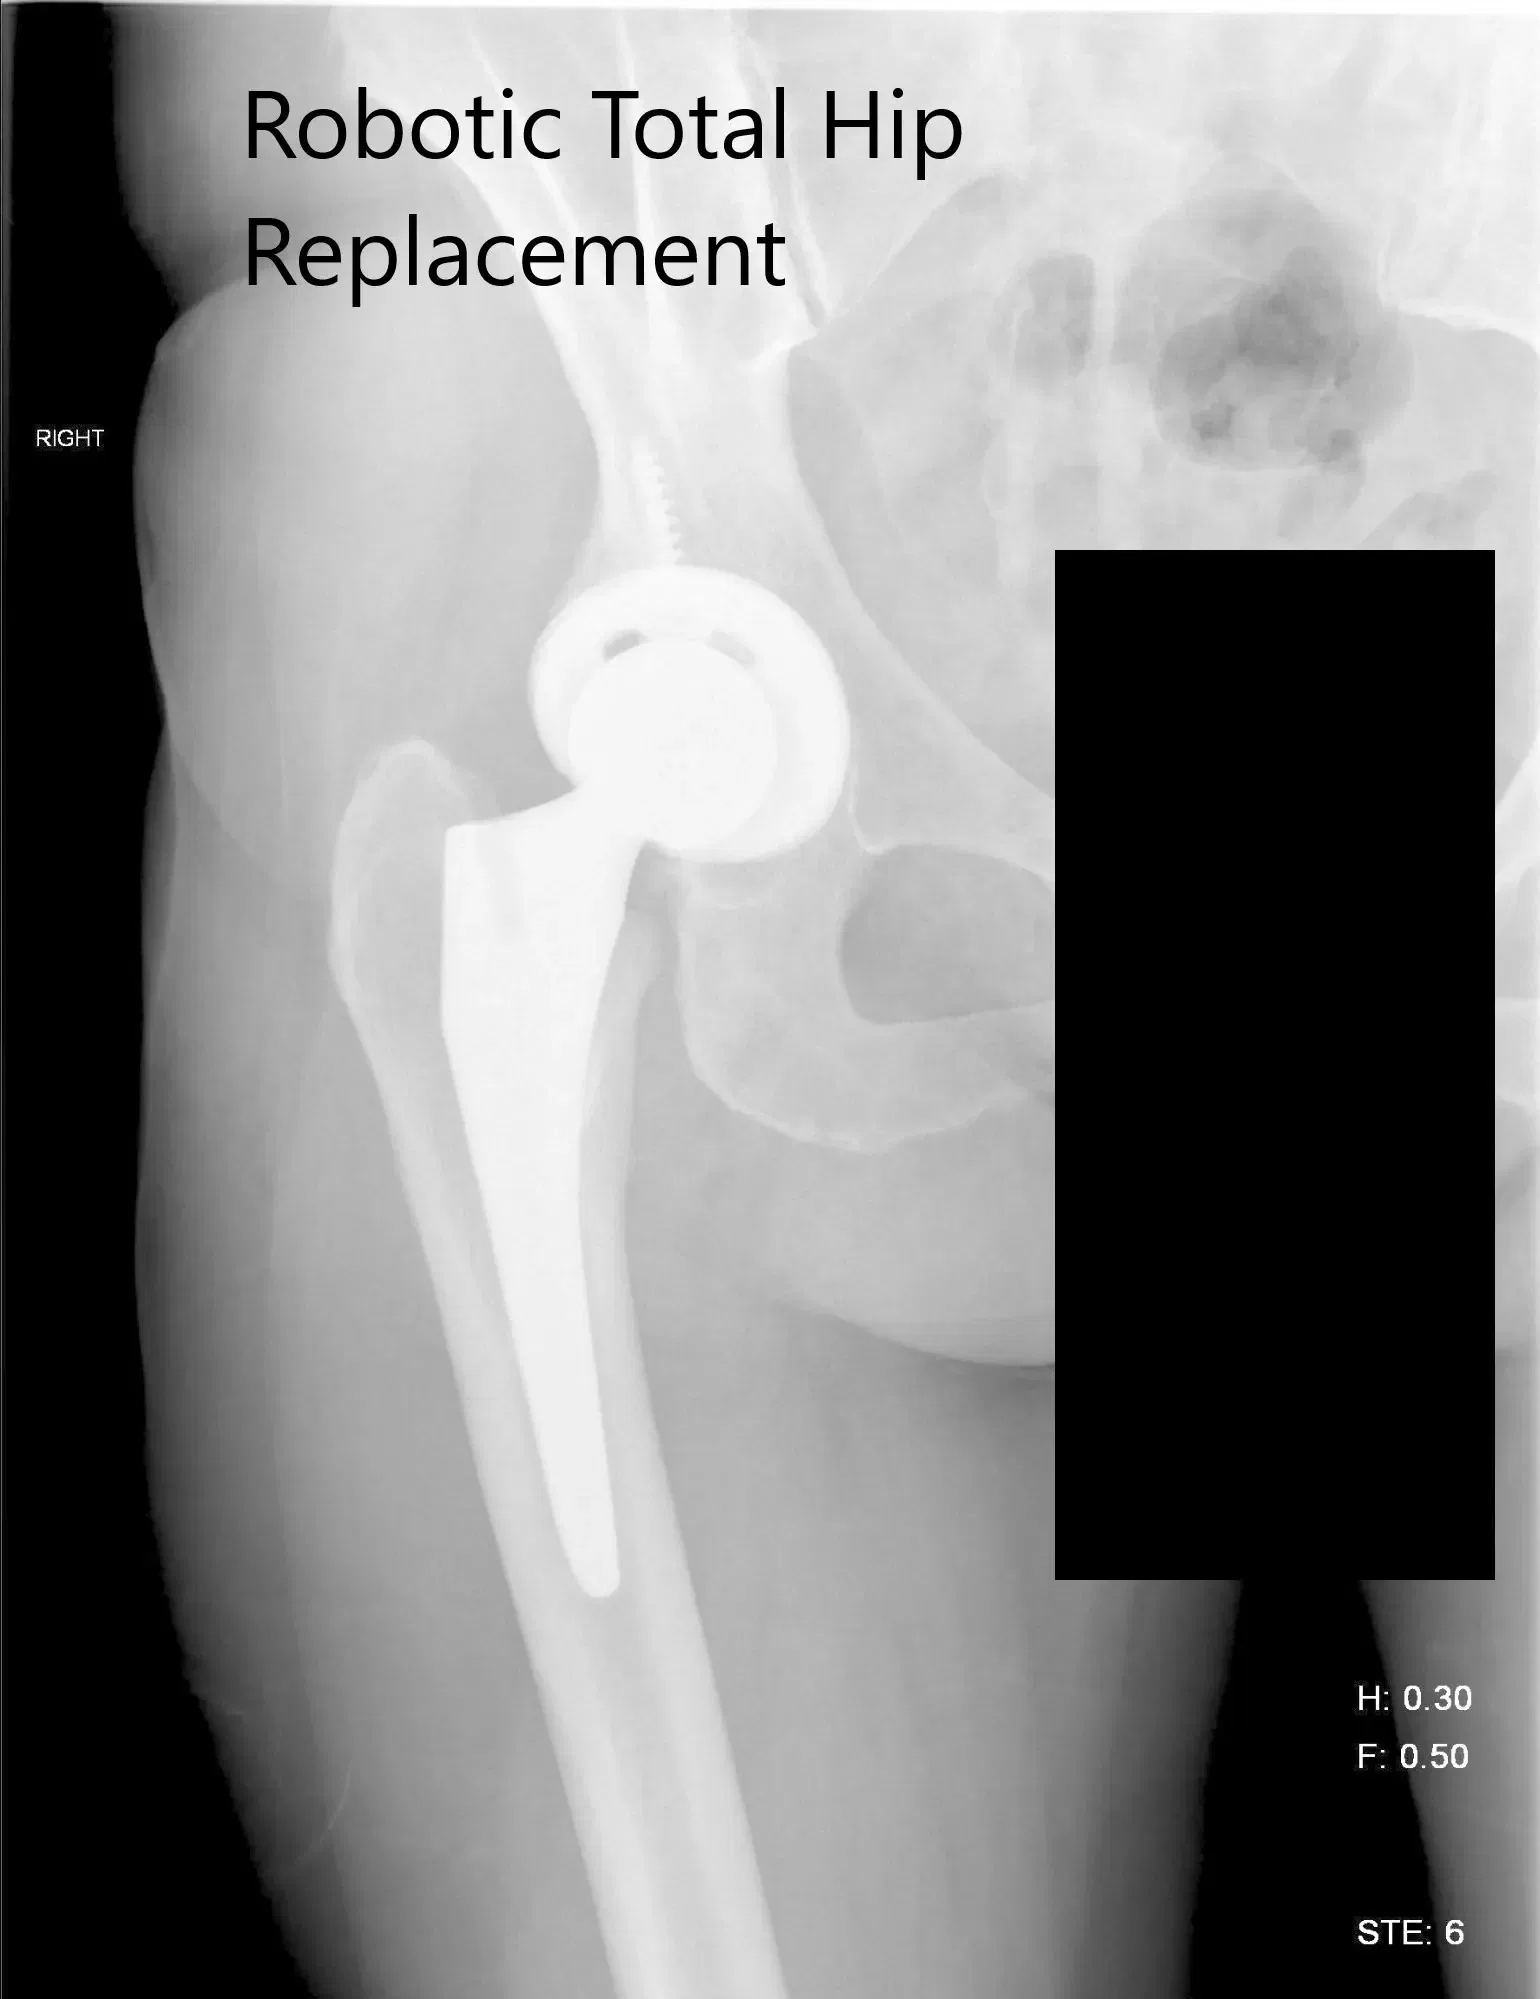

OPERACIÓN: Reemplazo total de cadera robótico derecho.

IMPLANTES UTILIZADOS: Carcasa de tritanio de 52 mm con tornillo de 6,5 mm x 30 mm y carcasa Trident. Cero grados de poliuretano con un vástago de 127 grados y cabeza cerámica, diámetro exterior de 32 mm menos 4.

Radiografía postoperatoria de la cadera derecha que muestra visión AP y lateral.